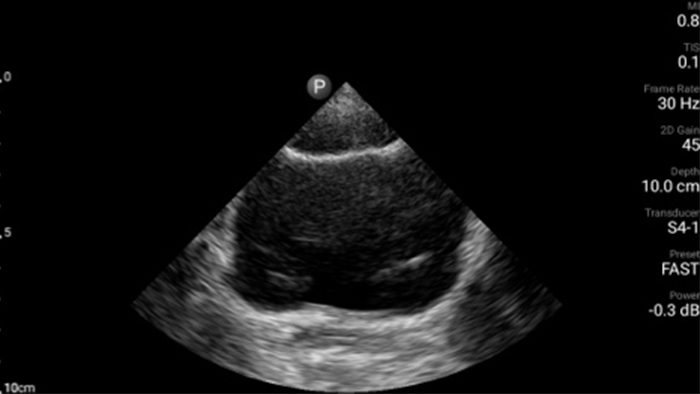

Echografieonderzoeken kunnen helpen om huidabcessen te identificeren en succesvol te behandelen.

Lumify kan helpen de subtiele details van een beeld zichtbaar te maken en afwijkende weefselstructuren bloot te leggen vanuit verschillende hoeken. Hierdoor kunt u met vertrouwen realtime beslissingen nemen, van diagnose tot herstel.

POC-echografie voor zacht weefsel